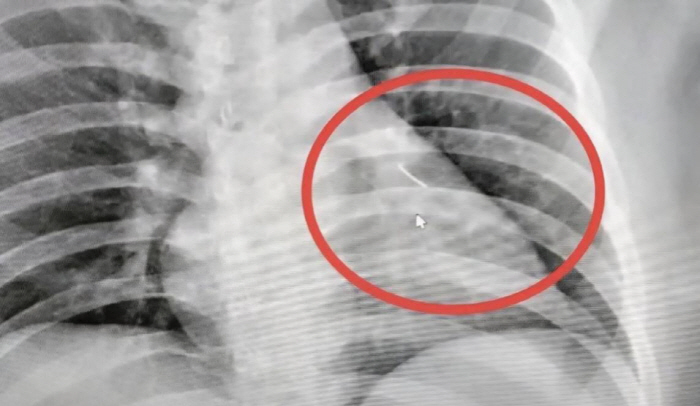

[스포츠조선 장종호 기자] 가슴 통증을 호소한 남성의 심장 부근에서 약 7cm 길이의 바늘이 발견돼 충격을 주고 있다.

외상 흔적은 없었지만, 병원 검사 결과 심장 근처에 날카로운 물체가 박혀 있는 것이 확인됐다. 해당 물체는 길이 약 7cm의 바늘이었다.

의료진은 즉시 응급 수술을 진행, 바늘을 제거했다.